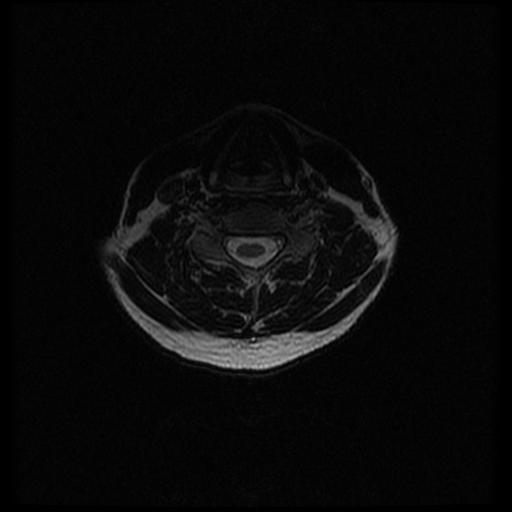

MRI Spine - Transverse

T2-Weighting

This study looks at the spine with 30 transverse (horizontal) cuts beginning at shoulder level working upward using a 0-axis Fast Relaxation Fast Spin Echo sequence.

Cervical images begin below shoulder level - around the mid-thoracic vertebra and end at the top of the spine - about level with the upper teeth and middle ear.